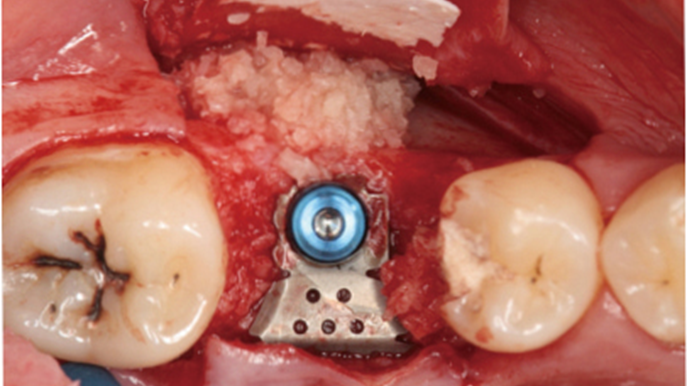

Clinical case: Installation of dental implants in complicated anatomic conditions using crest lifting methods

- Courtesy of Dr.Alexander Lysov, Russia -

Keywords

AnyRidge, complicated anatomic conditions, crest lift, MICA Kit, Dr. Alexander Lysov, bone regeneration, GBR, #26, maxillary posterior

Products:

AnyRidge implant system, MICA Kit

“Thin ridge expansion with minimally invasive surgery!

Use SmarThor & AnyRidge to place a wider diameter implant with minimal drilling after ridge splitting, even in thin ridge under 2mm! “